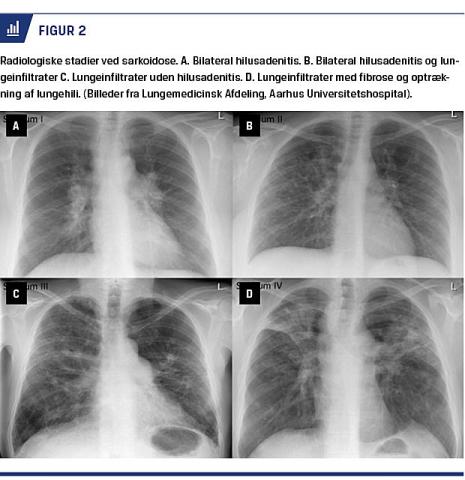

Radiologisk inddeles pulmonal sarkoidose i fem stadier, som ses ved røntgenoptagelse af thorax i to plan og har betydning for vurdering af aktivitet, behandling og prognose (Figur 2): Stadium 0: normalt røntgenbillede af thorax. Stadium I: bilateral forstørrelse af lymfeknuder i lungehilus/mediastinum uden lungeinfiltrater. Stadium II: forstørrede lymfeknuder i lungehili/mediastinum med lungeinfiltrater. Stadium III: lungeinfiltrater uden hilusadenitis og uden tegn til fibrose. Stadium IV: lungeinfiltrater med fibrose, cystedannelse og skrumpning af overlapperne med optrækning af lungehili (end-stage disease).

high resolution-CT (HRCT) af thorax ses parenkymforandringer som perihilære infiltrater og mikronoduli med perilymfatisk distribution (stadium II, III og IV) og apikale fibrotiske forandringer (stadium IV).